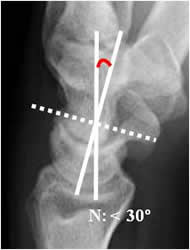

Angulo grandelunado:

En la inestabilidad tipo DISI (dorsal inestabilidad del segmento intercalado), se aprecia desplazamiento anterior y angulación dorsal del lunado, con aumento de los ángulos escafolunado por desplazamiento anterior del escafoides y del grandelunado por desplazamiento dorsal del lunado (27, 28). (Fig 53 y 54).

Fig 54. Inestabilidad tipo DISI.

A: Rx lateral de muñeca. Angulo escafolunado mayor de 60.